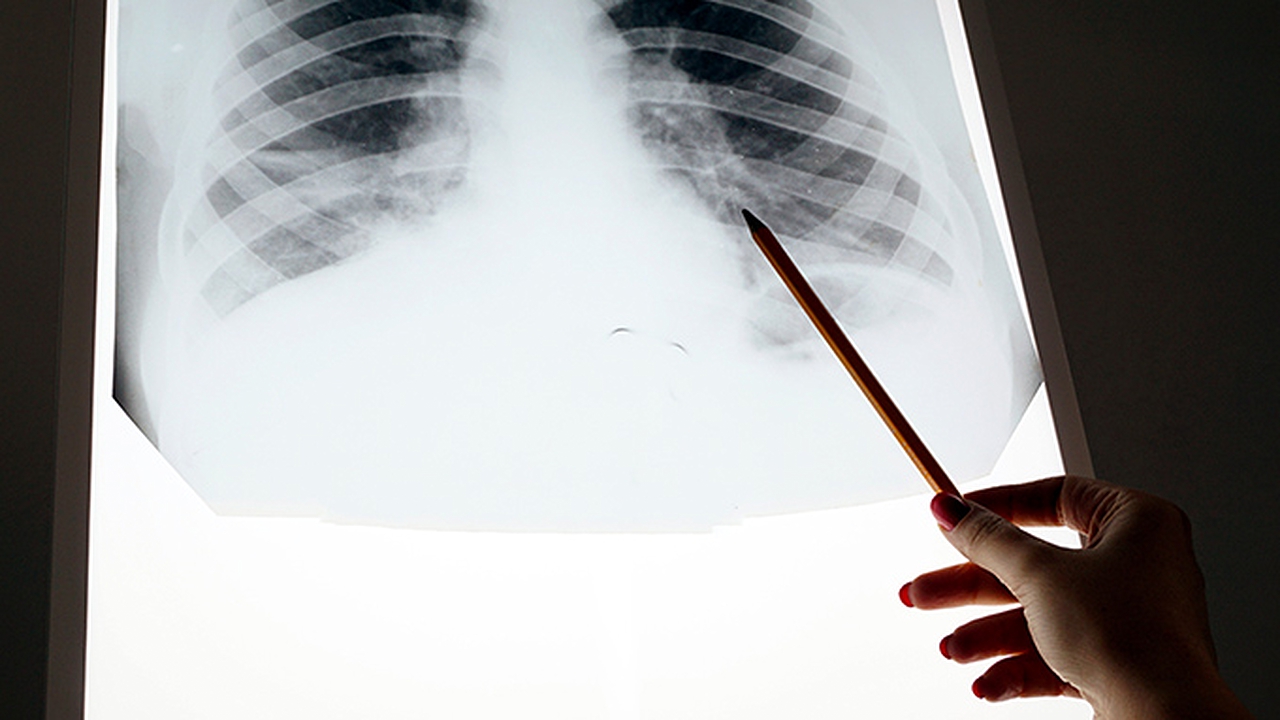

慢阻肺是一种常见的慢性呼吸系统疾病,主要由长期吸烟、空气污染等因素引起,表现为持续性气流受限。早期诊断和规范治疗对控制病情进展至关重要。